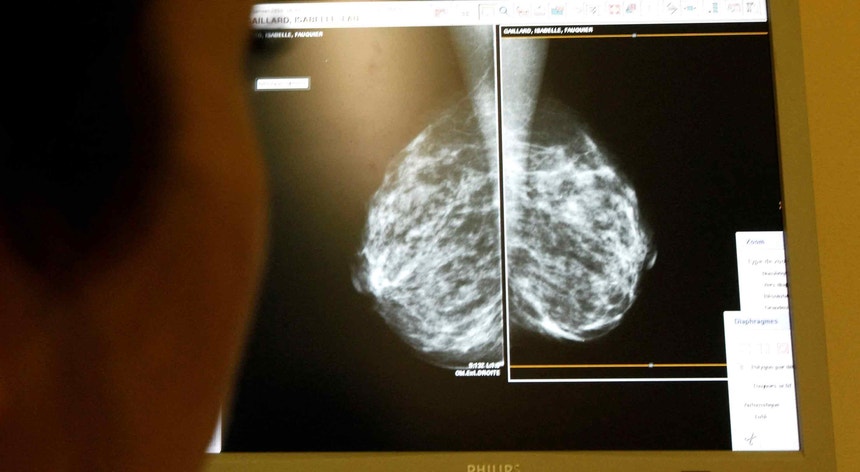

Adaptar tratamento do cancro da mama à resposta permite evitar quimioterapia, revela estudo

Um estudo apresentado na sexta-feira revela que adaptar a terapia do cancro da mama em função da resposta permitiu a um terço das pacientes evitar a quimioterapia em tratamentos onde era usada por defeito até agora.

O estudo em que participaram investigadores de 45 centros médicos de sete países europeus, incluindo Portugal, ajusta o tratamento em função da resposta, permitindo assim evitar a quimioterapia como resposta padrão.

O estudo concluiu que 37,9% das pacientes que foram tratadas sem recurso a quimioterapia conseguiram uma resposta patológica completa, e 95,4% não teve uma recaída até três anos depois.